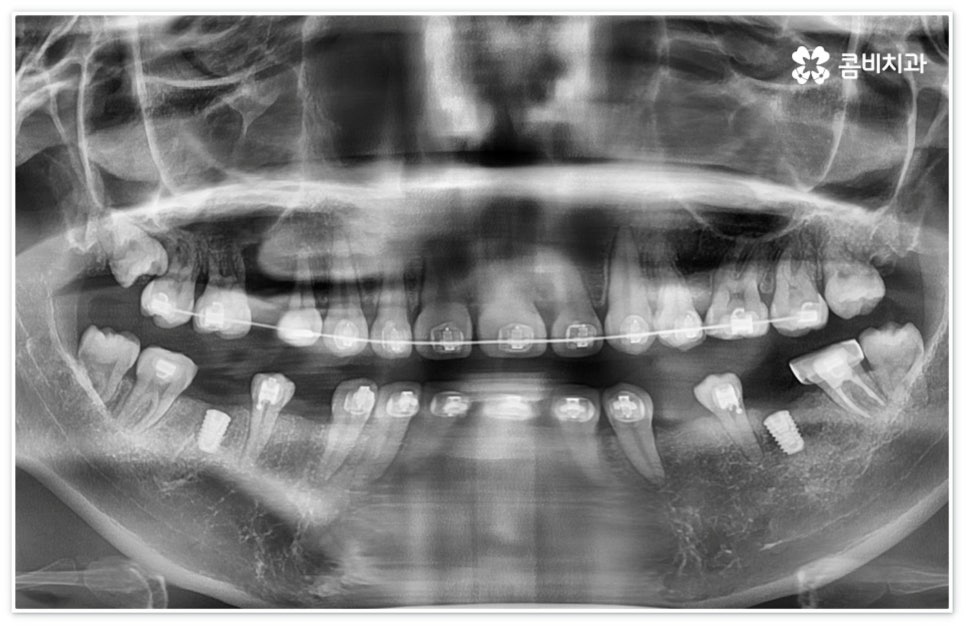

신경치료는 자연 치아를 보존할 수 있는 거의 마지막 단계의 치료라고 할 수 있으므로 만약 이 시기도 놓쳐서 신경치료를 할 수 없을 정도로 치아에 손상이 심각하다면 발치 후 임플란트 식립을 진행해야 할 거예요. 현대에 임플란트 관련 기술이 많이 발달하여 보다 편안한 사용이 가능해졌다고 하지만 자신이 타고난 치아를 따라갈 수는 없을 것이기 때문에 될 수 있는대로 자연 치아의 수명을 늘리는 방향으로 보존 치료를 해 줄 필요가 있는데요. 그러나 구강 질환이나 사고 등을 이유로 신경치료 등으로도 살릴 수 없이 이미 수명을 다한 치아의 경우 기능적으로나 심미적으로나 빠르게 대체해 주어야 할 거예요.

이때 환자분들마다 상황이 다를 수 있는데 예를 들어 교정 치료 중 충치 치료 (신경 치료) 및 발치와 임플란트 식립과 같은 고난도의 치료들을 함께 진행해야 하는 복잡한 케이스의 경우에는 더욱 시술자의 숙련도가 중요하다고 할 수 있어요. 의료진의 자격증, 경력 사항, 분과별 협진 여부 등을 잘 알아 보시고 필요한 치료들을 모두 통합적으로 진행할 수 있는지, 또한 환자분들의 상황을 꼼꼼하게 살필 수 있는 3D CT 와 같은 정밀 검진 기계를 갖추고 있는지 등을 체크해 보신 후에 처음부터 끝까지 책임 진료하는 의료진과 철저한 케어 시스템을 갖추고 있는 치과를 선택하셔서 제 때 필요한 치료를 받으시길 권유드리고 있습니다.